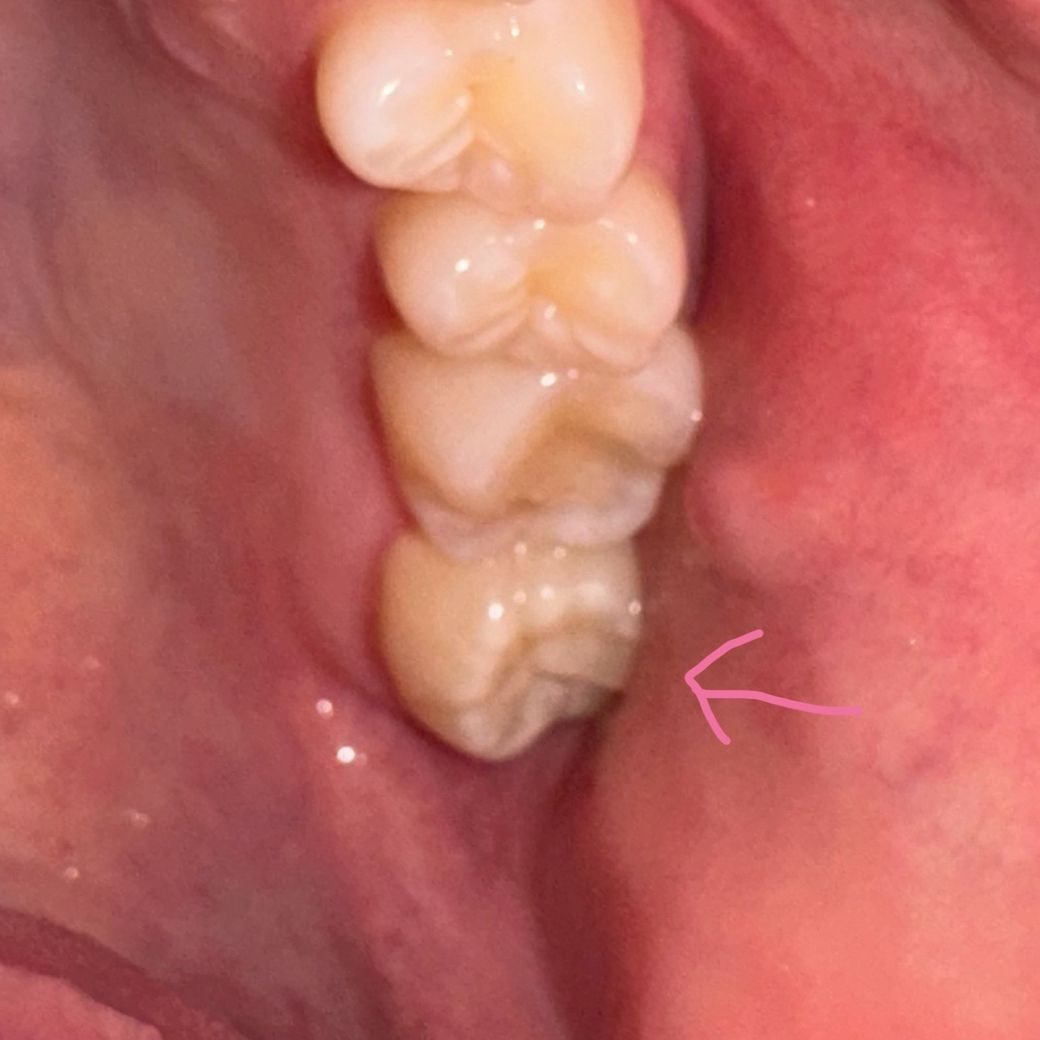

제2대구치 큰어금니가 없는데 임플란트 대신 발치하고싶어요

원래 아래쪽 큰어금니가 없어서 치과에서는 임플란트를 하라고 했는데요..

그래서 일단 냅뒀더니 위쪽 큰어금니가 계속 자라면서 양치도 잘 안돼고 좀 아파져서요ㅜ 가끔 아래쪽 잇몸도 부아오르고

그럼 그냥 자라고있는 위쪽 큰어금니를 빼버리면 안되나 싶어서요..

어차피 지금 맞물리는 치아가 없으니까 얘는 있으나마나한거 아닌가요??? 그럼 그냥 뽑아버려도 되나요?

엑스레이가 한 반년전이고 사진이 지금이에요

• 1번 째 사진

1. 말씀하신 것처럼 지금 왼쪽 맨 뒤 어금니는 아래와 맞닿는 치아가 없어서 위에 치아는 계속 정출되고, 잇몸 염증 유발합니다.